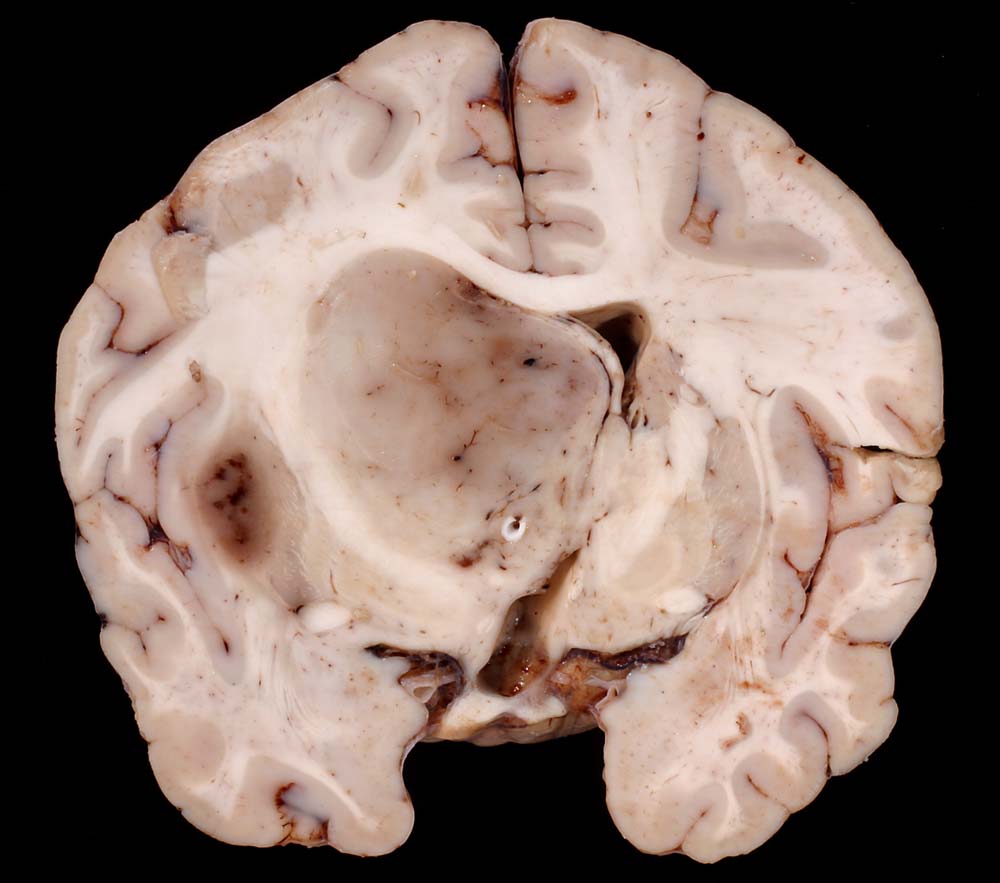

Makroskopisch sind die Tumoren gut begrenzt, solide und graurosa. Fokale Verkalkungen sind häufig, Nekrosen und zystische Degeneration können vorkommen. Intratumorale Einblutungen sind oft vorhanden und können die Todesursache darstellen.

• Fokale mukoide/zystische Degeneration innerhalb des Tumors mit Ausbildung von Pseudozysten.